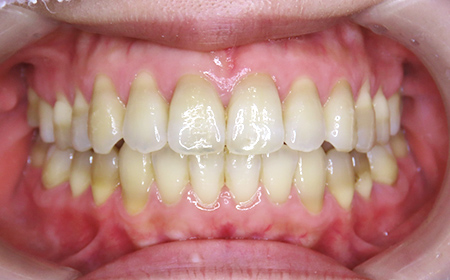

CASE02

Before

After

| 施術名 |

インビザラインGoを用いた矯正治療(叢生) |

| 治療期間 |

4ヶ月 |

| 治療費 |

437,800円(税込) |

| リスク |

マウスピース装置により疼痛・咬合時痛を生じる事があります。割れたり壊れたりする事があります。 |

歯科医師からのコメント

人と話す機会の多いご職業で、以前より「前歯のがたつき」が気になるとのことでご相談にいらっしゃいました。仕事中も目立たず、仕事に支障がでなくてよかったと仰っており、とても満足しておられました。